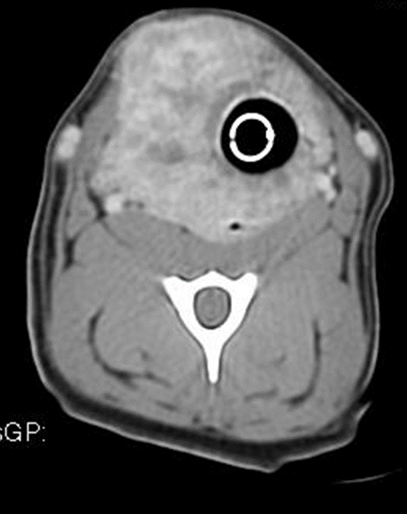

Thyroid cancer is most often discovered when a mass on the neck is noticed by a pet owner. Thyroid tumors in dogs are not very common and only account for one to four percent of all canine tumors. Dogs can sense it, thanks to their sense of smell that is 10 times better than a human's, much easier and faster than any medical testing. T3 is the more potent hormone. What kind of dog it is? Thyroid cancer can be particularly hard to diagnose, and with any type of cancer it can be tough to tell if the patient is 100% cancer free following treatment. A trained scent dog was able to accurately identify thyroid cancer in urine samples from patients with thyroid nodules. Surgery, radiation therapy, or radioactive iodine are potential treatment options. A type of cancer, called thyroid carcinoma, is the primary cause of hyperthyroidism in dogs. You may notice that your dog has a mass on the neck. Thyroid tumors in dogs and cats tend to have very different behaviors. Thursday, march 26, 2015 by: How common is cancer in dogs, and what are some of the common cancers found in dogs?

The Endocrine Glands In The Dog From The Cell To Hormone Intechopen from www.intechopen.com If you notice a mass in your dog's neck, don't panic just yet! Using dogs already trained for scent detection, researchers led by donald bodenner trained them to detect cancer by presenting them with fresh tissue taken from papillary thyroid carcinoma biopsies. Thyroid gland adenocarcinoma in dogs. There may be a breed predisposition for boxers, beagles. When cancer starts in the thyroid gland, it is called thyroid cancer. The thyroid glands are paired structures located along the windpipe (trachea), about halfway thyroid growths in your dog can be benign (adenoma) or malignant (carcinoma). Thyroid cancer can be particularly hard to diagnose, and with any type of cancer it can be tough to tell if the patient is 100% cancer free following treatment. There have been cases of thyroid cancer growing on the neck in an area away from the thyroid, and in the chest or under the tongue.

Thyroid cancer is most often discovered when a mass on the neck is noticed by a pet owner.